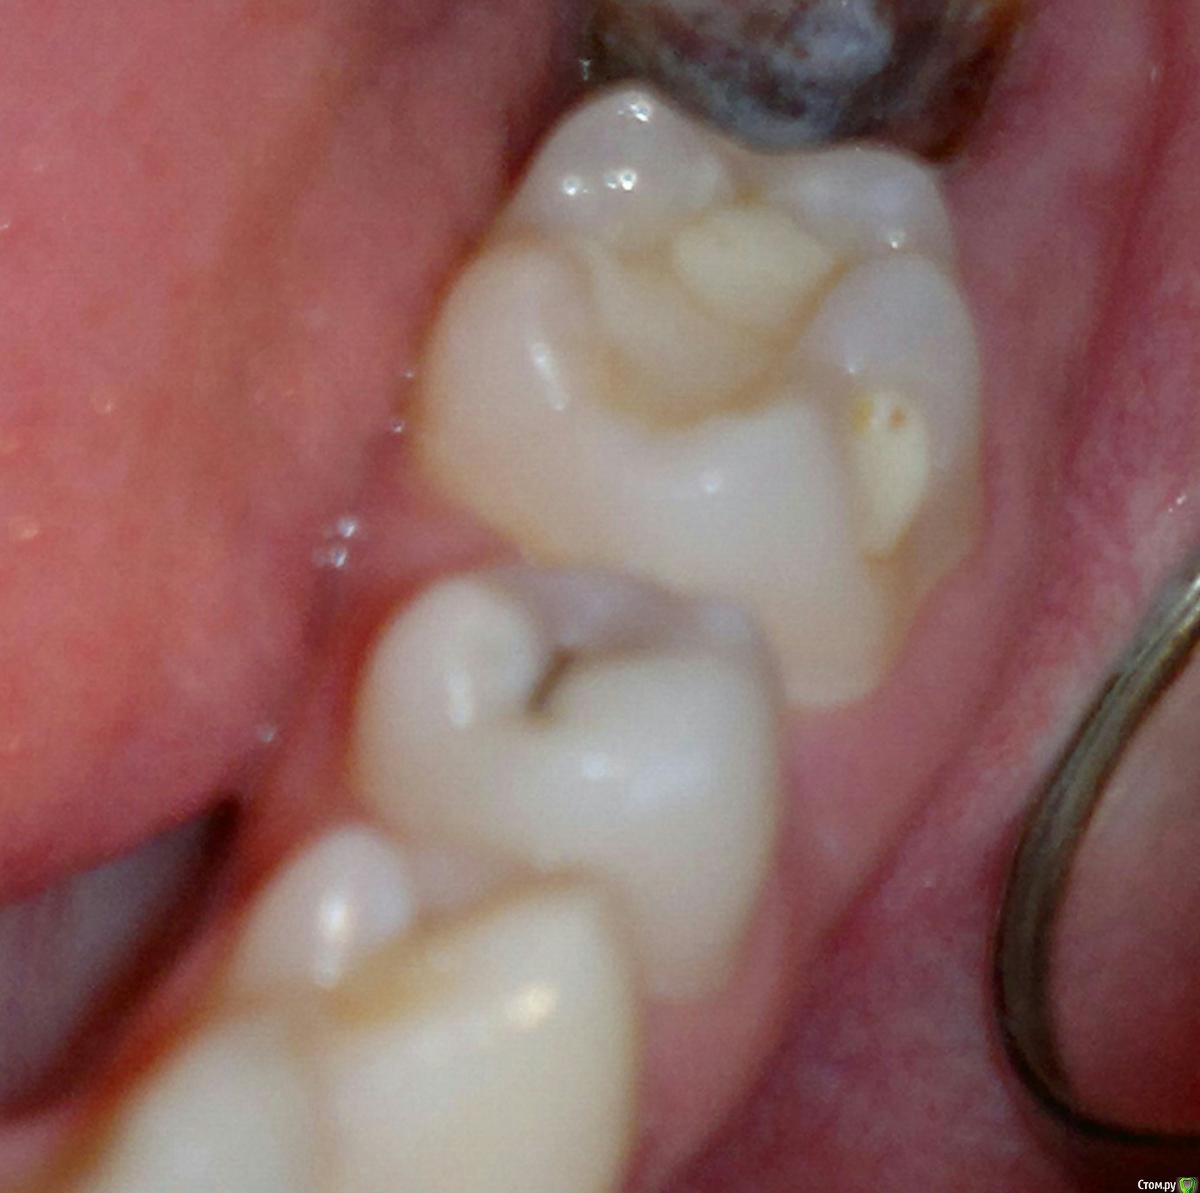

igorstom Опубликовано 24 ноября, 2019 Автор Поделиться Опубликовано 24 ноября, 2019 Ещё один пример кариеса корня зуба 3.7. Но в данном случае он неглубокий. Понятно, что световые пломбы к цементу корня не фиксируются, и 100% будет нарушение краевого прилегания, и отсюда вторичный кариес. Вопрос. Как же выйти из ситуации в данном случае, если световые пломбы в месте прилегания к корню не фиксирутся? Потом расскажу, как делаю я. Но хотелось бы услышать другие мнения. Может у кого-то есть идеи получше, чем мои решения..И да, сразу пример по поводу перелечивания каналов. Я берусь за перелечку чужого эндо, но только платно. 1 Ссылка на комментарий